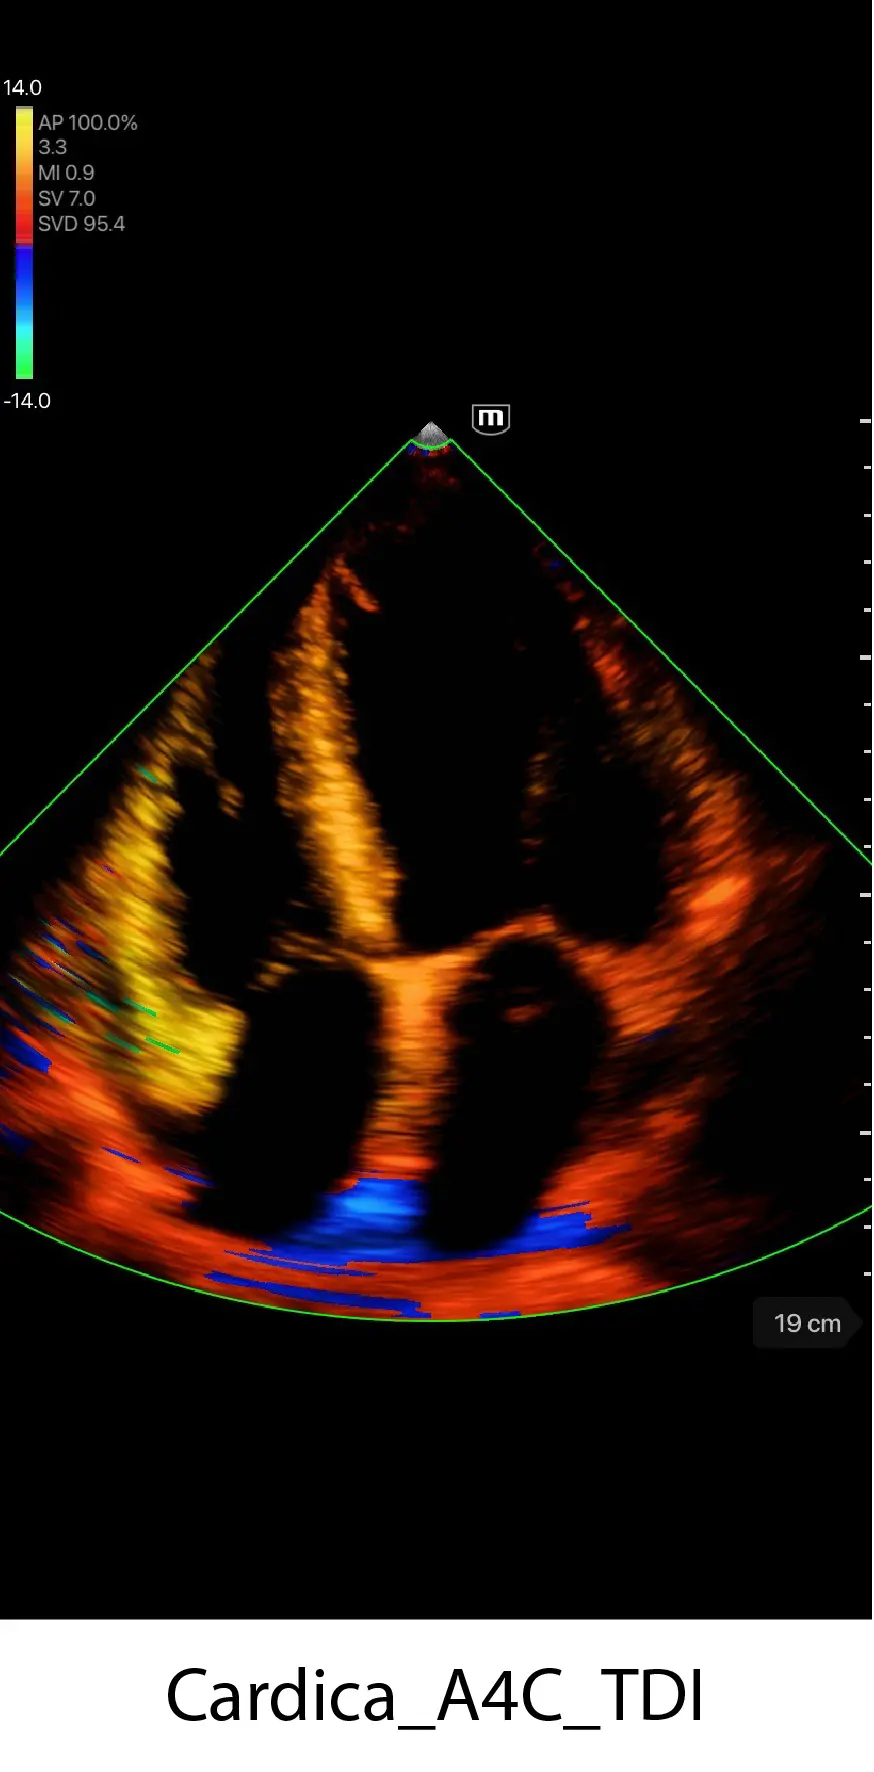

Професионално качество на диагностичните изображения

Предварително зададени приложения

Различни режими на изображението

Множество режими за сканиране

B mode

Color mode

M mode

PW mode

Power mode

TDI (опция)

Клинични снимки